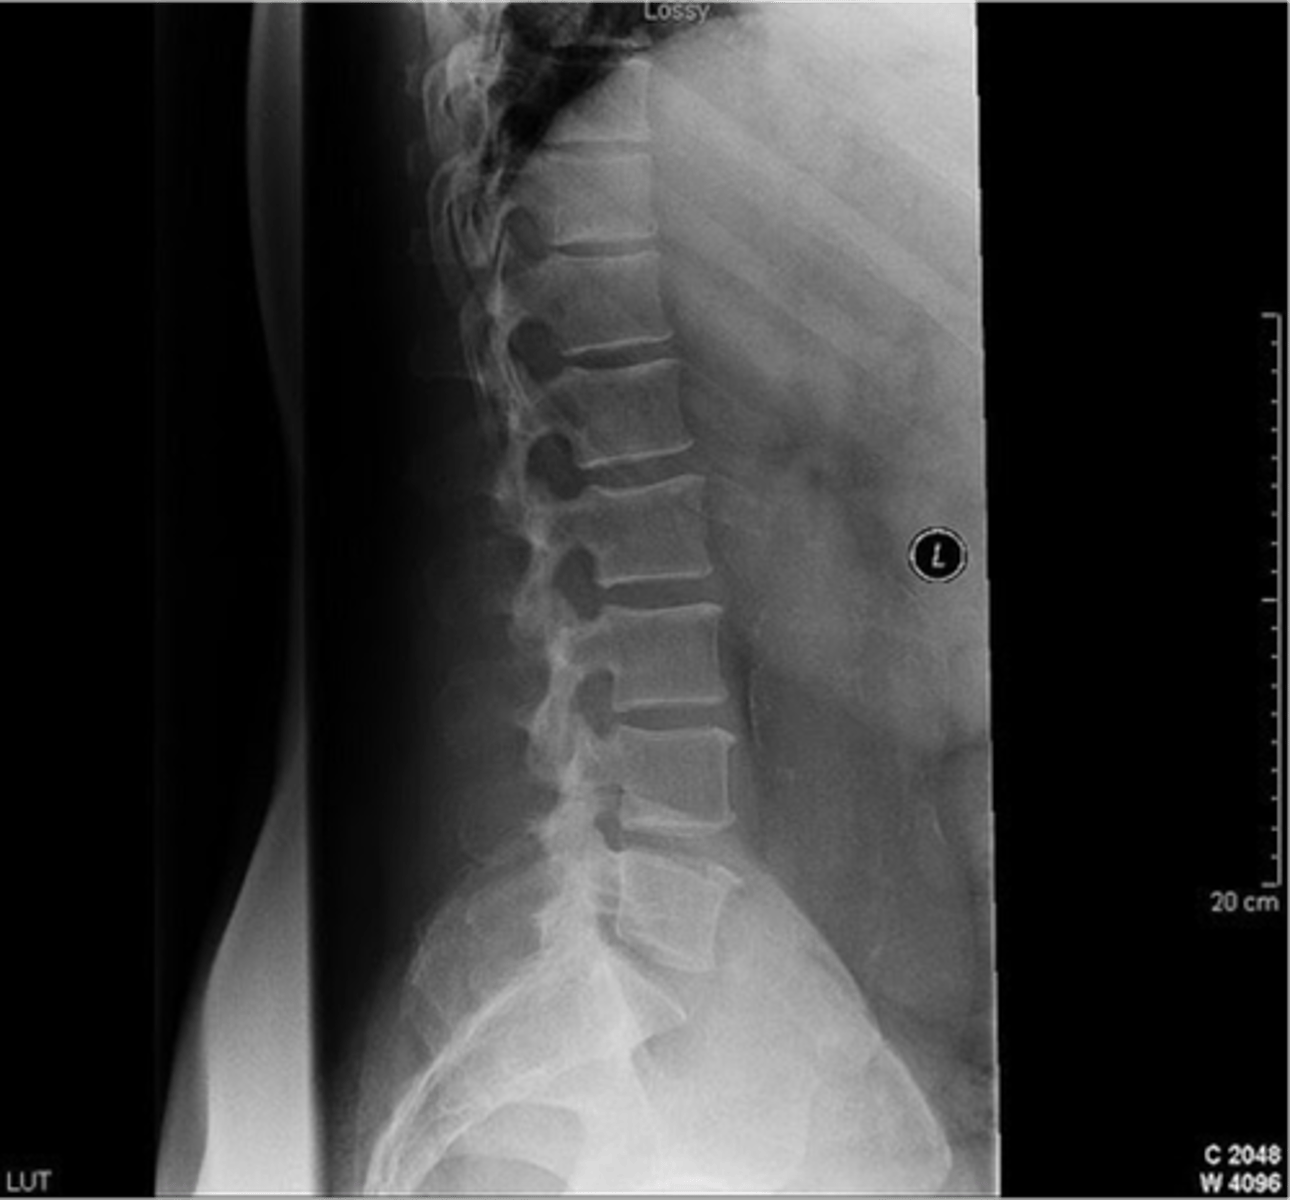

what is wrong

could be muscle strain or a HNP

difference between cauda equina and HNP

cauda equina comes out medially

HNP comes out laterally